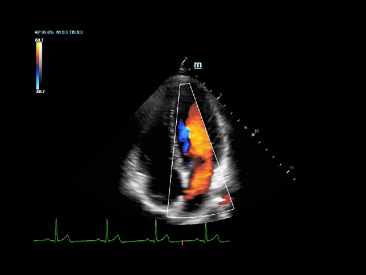

eXceeding Experience

Erfahrung mit hoher Produktivit?t

eXceeding Experience mit dem Scannen erlaubt die st?rkere Fokussierung auf Patient und Patientin sowie die Qualit?t der Untersuchungsergebnisse sowohl in Bezug auf Klarheit als auch auf Benutzerfreundlichkeit. Das X-Insight bietet eine au?ergew?hnlich einfache Bedienung mit besserer Ergonomik, einfacherem Scannen und flexiblem Management und ├╝bertrifft Ihre Erwartungen wom?glich sogar.